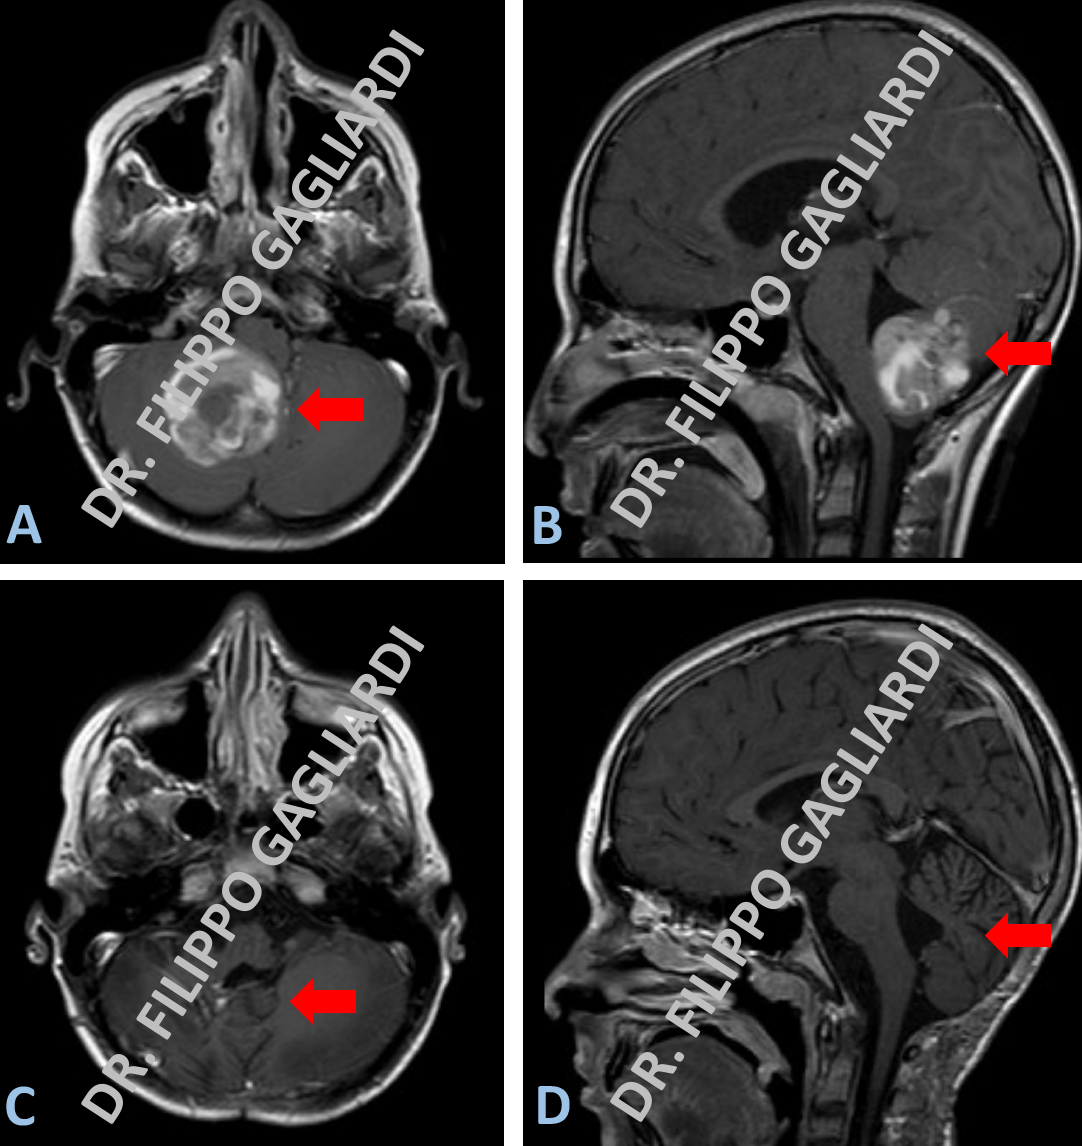

Exeresi di astrocitoma pilocitico cerebellare

Caso di astrocitoma pilocitico, tumore primitivo del cervelletto, in una bambina di 10 anni con vomito e cefalea. Le figure A e B mostrano rispettivamente la sequenza assiale e sagittale (laterale) della RM pre-operatoria. La voluminosa lesione prende contrasto in modo disomogeneo. Condiziona la compressione del cervelletto e del tronco cerebrale (struttura anatomica ad altissimo contenuto funzionale, che regola l’attività cardiaca e respiratoria). La giovane Paziente è stata sottoposta ad intervento di craniectomia sub-occipitale ed exeresi radicale della lesione. Le figure C e D illustrano il controllo post-operatorio, dove non si apprezza più il tessuto patologico.